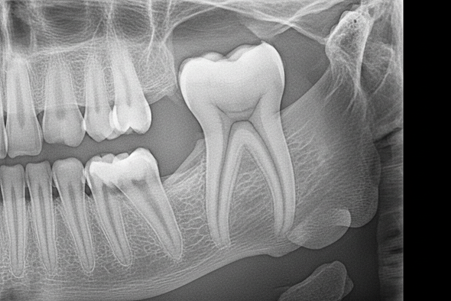

عکس پری اپیکال (Periapical) تصویری دقیق از کل دندان، از تاج تا نوک ریشه، و استخوان اطراف آن است. این عکس رادیوگرافی دندان در بررسی عفونتهای اطراف ریشه (مانند آنچه که نیاز به عصب کشی در کاشان دارد) و ارزیابی پیشرفت بیماریهای لثه اهمیت دارد و برای تشخیص عفونت دندان لازم است.

رادیوگرافی دندان شامل روشهای مختلفی است که هر کدام اطلاعات خاصی را برای تشخیص وضعیت ساختار دندان انسان و بافتهای اطراف آن ارائه میدهند. آگاهی از انواع این تصاویر، به ویژه OPG (پانورامیک) و عکس داخل دهانی (Bitewing)، در انتخاب درست روش تصویربرداری توسط متخصص دندانپزشکی در کاشان نقش دارد.

عکس پانورامیک دندان یا پانورکس opg دندان در کاشان، تصویری گسترده از تمام دندانها، فکها، و ساختارهای اطراف آن در یک فیلم واحد است. این عکس رادیوگرافی دندان برای ارزیابی کلی سلامت دهان و عکس دندان عقل بسیار کاربردی است. این روش دید خوبی برای ارزیابی کلی عکس دندان فک بالا و پایین به ما میدهد.

عکس داخل دهانی (Bitewing) در دندانپزشکی به منظور تشخیص پوسیدگی بین دندانها و ارزیابی ارتفاع استخوان اطراف آنها گرفته میشود. این نوع عکس رادیوگرافی دندان با قرار دادن فیلم یا حسگر داخل دهان انجام شده و در تشخیص پوسیدگی در مراحل اولیه بسیار دقیق است.